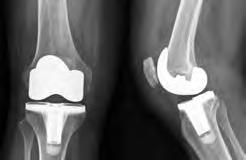

Substituição total do joelho

A substituição total do joelho também é designada artroplastia total do joelho. É uma cirurgia que se realiza para remover e substituir (ou trazer novamente à superfície) as partes desgastadas da articulação do joelho. O joelho é constituído pela extremidade inferior do osso da coxa (fémur), pela extremidade superior do osso da canela (tíbia) e pela rótula (patela), que desliza numa cavidade localizada na extremidade do fémur. Existem ligamentos de grandes dimensões ligados ao fémur e à tíbia, que servem para proporcionar estabilidade. Os músculos extensos da coxa proporcionam força ao joelho. As superfícies articulares que contactam com estes três ossos encontram-se cobertas de cartilagem articular, que amortece os impactos dos ossos e permite que os mesmos se movam com facilidade. Uma membrana fina liberta um fluido especial, que lubrifica o joelho e reduz o atrito durante o movimento. Normalmente, todos esses componentes funcionam em harmonia. Contudo, as doenças ou lesões podem provocar dor, fraqueza muscular e reduções da função. Se tiver esses problemas, poderá precisar de uma substituição total do joelho.

Durante a substituição total do joelho, as superfícies danificadas da articulação do joelho são removidas e substituídas por um implante. Esse implante poderá ser feito de metal e/ou plástico. A cirurgia de substituição total do joelho pode diminuir ou eliminar a dor no joelho e facilitar a permanência em pé, a posição sentada e o andar.

Articulação do joelho normal

Articulação do joelho implantada

Vista frontal Vista lateral